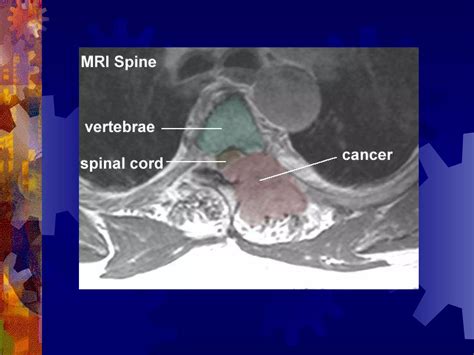

• Imaging Studies: Imaging tests such as MRI or CT scans to visualize the spinal cord and identify any structural abnormalities or damage.